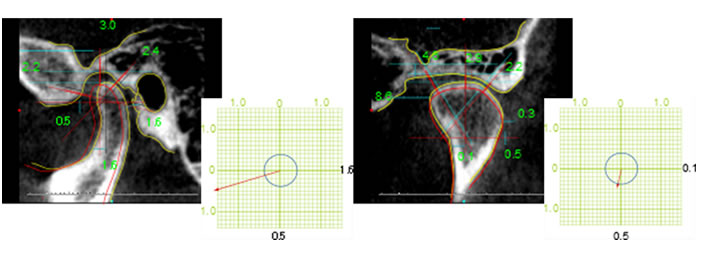

- CT精査撮影(SL)

- 顎関節 分析診断